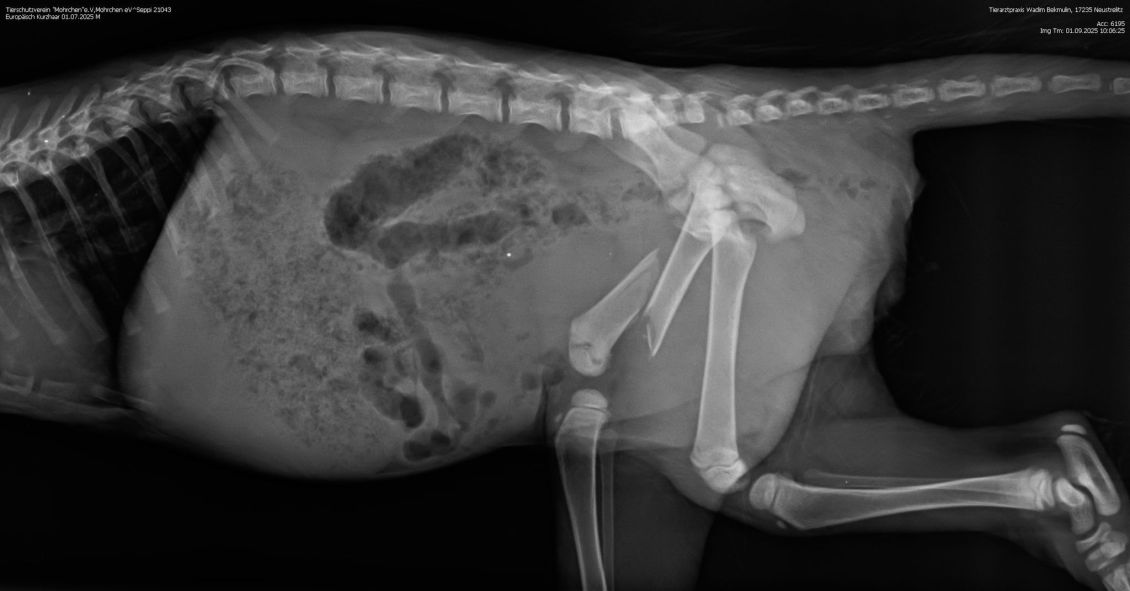

Nun kann es schnell gehen - und das ist auch nötig: Denn die Röntgenbilder zeigen,dass der Oberschenkel stark verschoben ist und ihm große Schmerzen bereitet.

Beim Tierarzt haben wir erfahren, dass Seppi einen schweren Oberschenkelbruch erlitten hat. Damit er schmerzfrei laufen kann und keine bleibenden Schäden entstehen,

muss der kleine Kerl dringend operiert werden. Die Kosten werden sich voraussichtlich auf ca. 1.300 Euro belaufen. Eine Summe, die wir nicht alleine stemmen können. Deshalb bitten wir um Hilfe. Jede Spende, egal in welcher Höhe, zählt. Unser Ziel ist es, dass Seppi eine gute Chance auf eine gesundes Leben erhält.